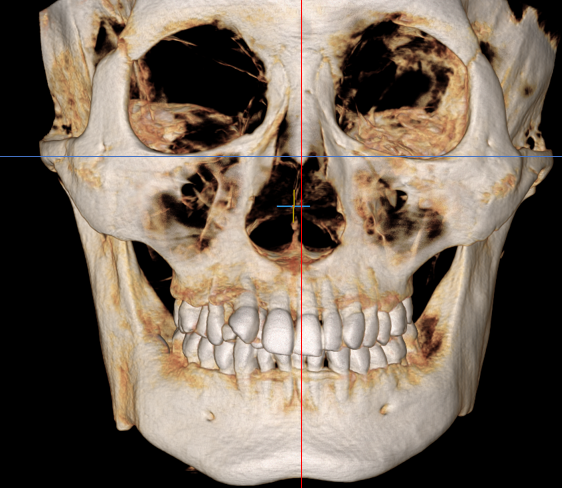

골격 대비 앞니 각도로 판단하는 비발치 교정

치아 배열만 보고 발치 여부를 결정하는 것이 아니라, 골격 구조와 앞니의 각도를 종합적으로 분석하는 것이 중요합니다.

얼굴 골격 구조에 비해 앞니가 안으로 기울어져 있다면, 이는 비발치로 개선해야 될 가능성이 높습니다.

이런 상태에서 발치교정으로 진행할 경우 앞니 각도가 더욱 안쪽으로 들어가면서 옥니가 될 수 있기 때문입니다.

따라서 이런 경우 이를 뽑지 않고, 기울어진 각도를 바로 세워주며 공간을 확보하고 배열을 개선하는 편입니다.

반대로 골격에 비해 앞니가 이미 많이 튀어나와 있거나 바깥쪽으로 기울어져 있다면, 발치를 고려해야 할 수도 있습니다.

이처럼 단순히 치아가 삐뚤하다는 이유만으로 발치를 결정하는 것이 아니라, 골격과의 관계를 면밀히 살펴야 합니다.

측면 엑스레이 촬영을 통해 두개골 대비 앞니의 각도를 측정하고, 이 수치를 바탕으로 비발치 가능 여부를 판단합니다.